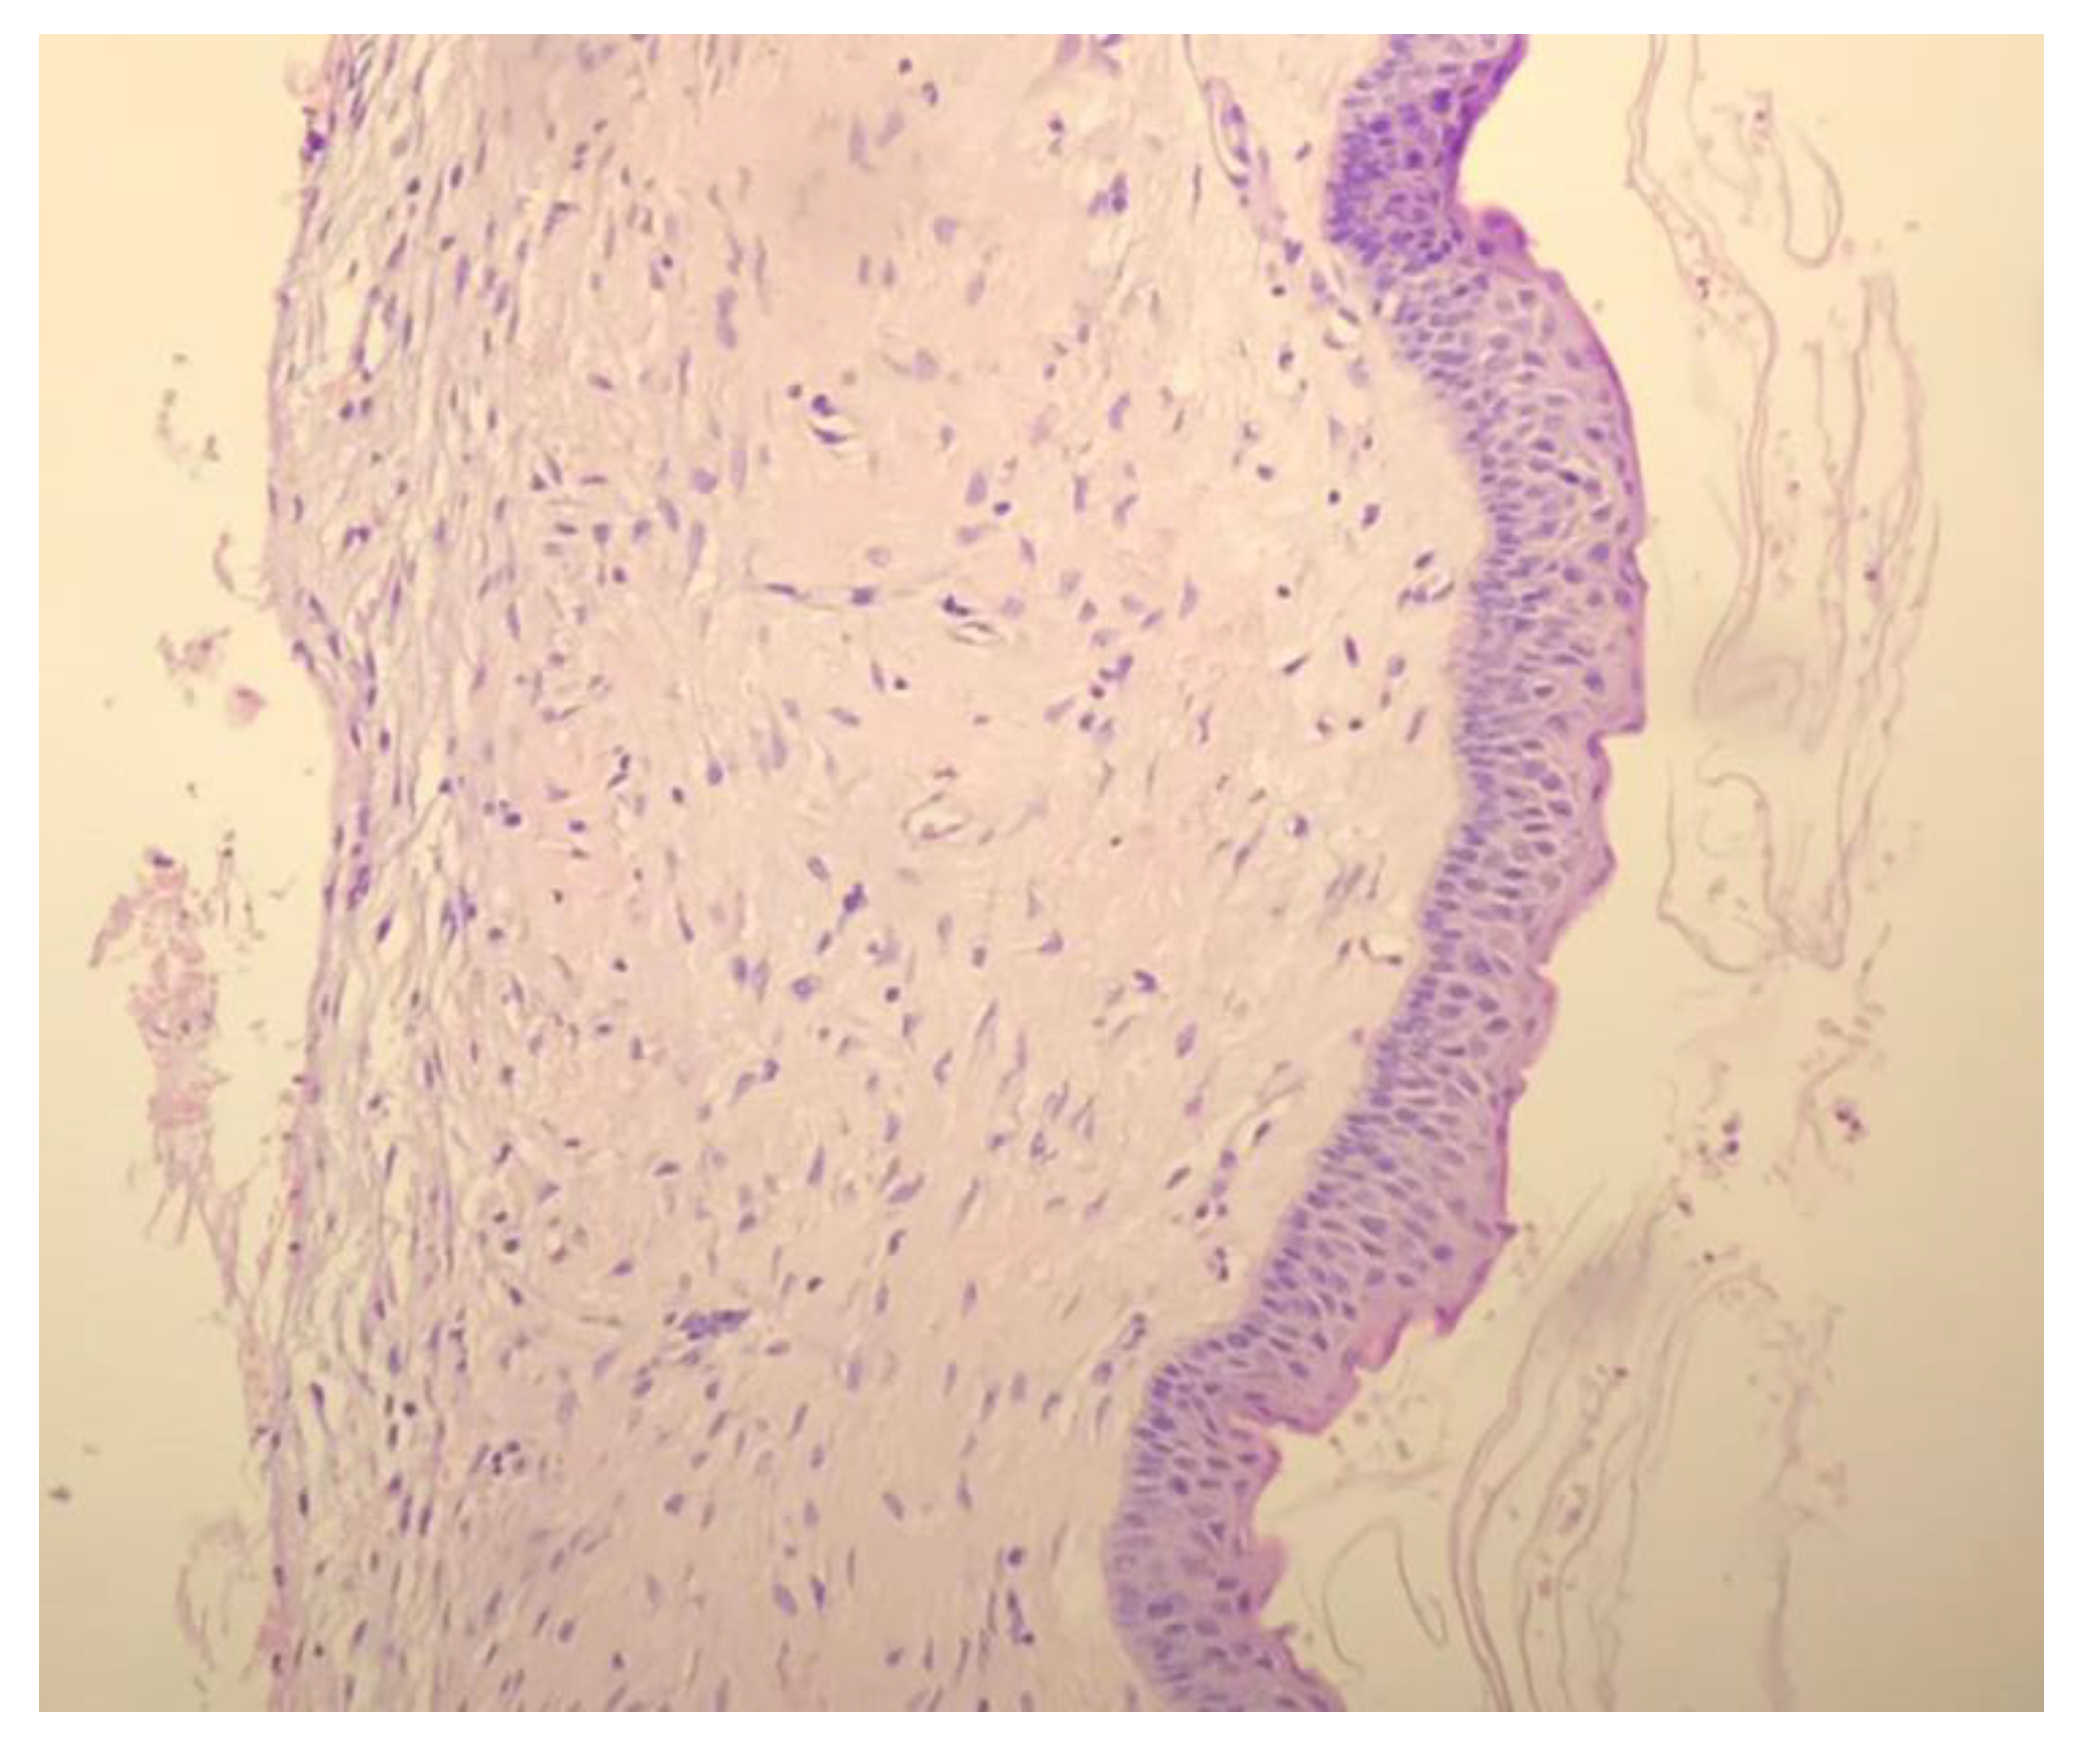

3. Results

4. Discussion